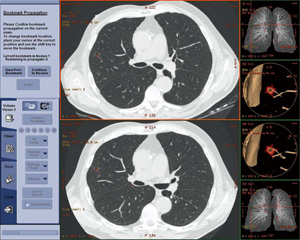

3D画像については「Centricity AW Suite」を使用することにより,2Dと同時に3D画像を表示し連動させることが可能となっている。「Centricity RA1000」から起動が可能なため,スタンドアローンタイプの3D WSに移動する必要がない(図2)。最新のAW Suite では,“Advanced Vessel Analysis”,“Card IQ”など,「Advantage Workstation」で定評のあるアプリケーションを搭載している。特に,肺の病変診断をサポートする“Lung VCAR”(図3)においては,画像診断におけるアシストアプリケーションとして,結節の描出,体積などの値を経時的にとらえることが可能になっている。作成されたデータは,スクリーンキャプチャーはもちろん,3Dボリュームデータでの保存も可能であるため,複数のユーザーがデータを共有,加工することも可能である。

図3 3Dでの過去画像との比較が可能なLung VCAR